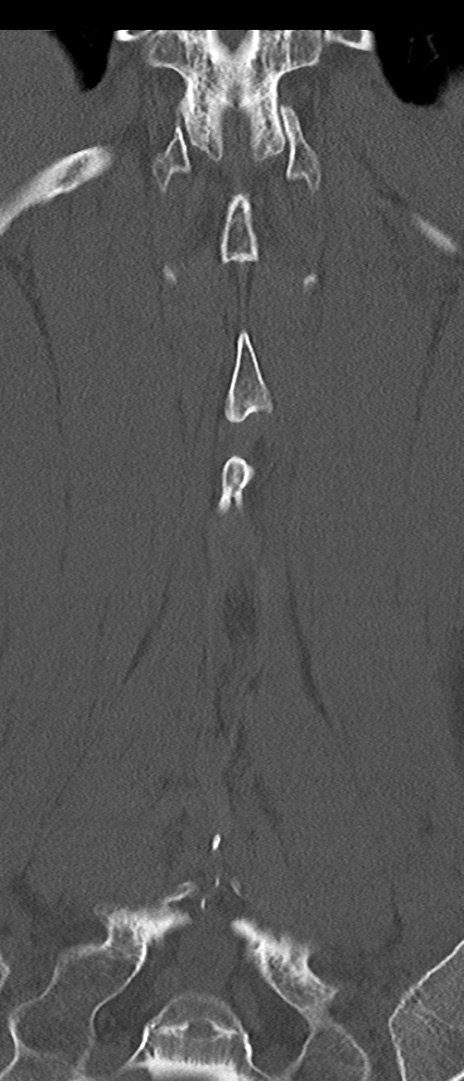

腰椎CT

矢状断像